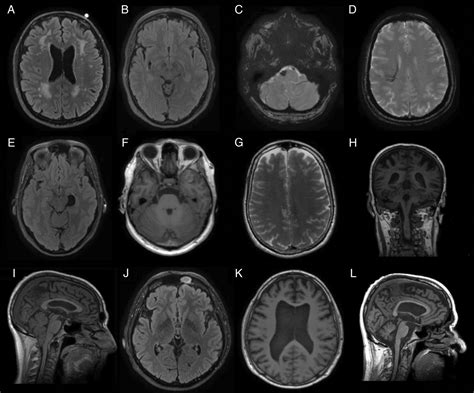

When you undergo this procedure, the radiologist evaluates several key components to ensure everything is within expected limits:

• Ventricular System: Examining the fluid-filled spaces of the brain to ensure they are the correct size and shape.

• White and Gray Matter: Ensuring the tissue density and distribution are consistent with healthy neural architecture.

• Brain Stem and Cerebellum: Checking for clear structures at the base of the brain responsible for vital functions.

• Major Blood Vessels: Assessing for signs of vascular abnormalities, such as aneurysms or stenoses.

• normal brain mri dwi

• normal brain mri axial

• normal brain mri t2